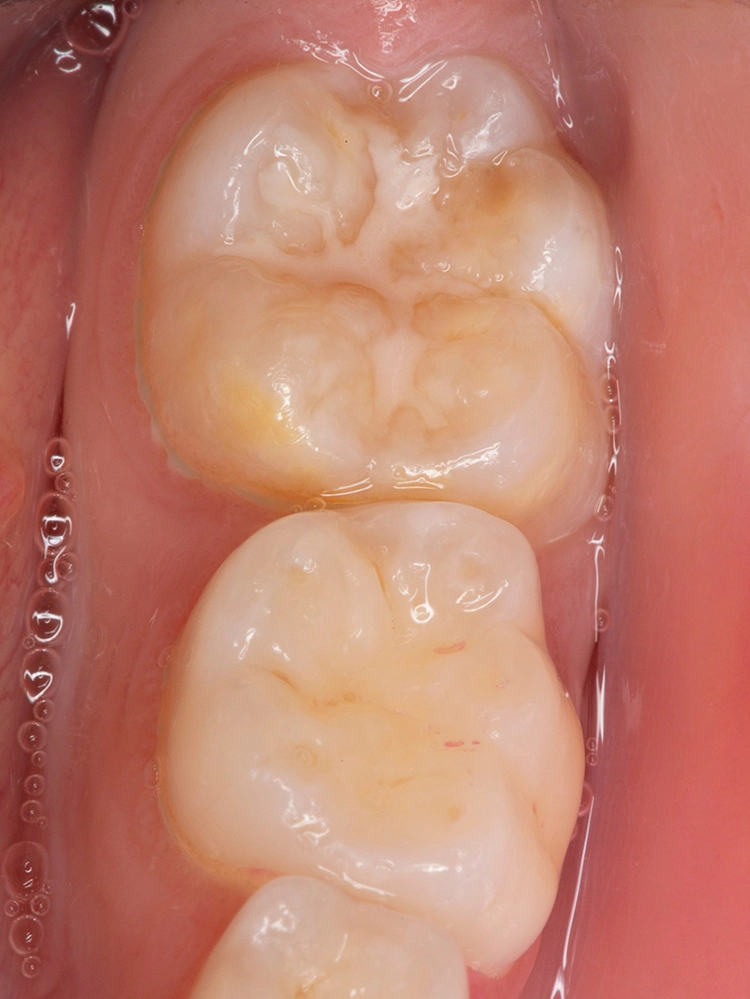

Bekes/BoukhobzaAbb. 5a–c: Posteruptiver Schmelzverlust und Kavitation an dem unteren bleibenden MIH-Molaren und anschließende

Füllungstherapie mit einem Komposit.

Aufgrund seiner Eigenschaften ist Komposit das geeignetste und zu favorisierende direkte Restaurationsmaterial bei MIH-Zähnen [14]. Es bedarf keiner retentiven Präparation, sodass die Füllung gezielt defektorientiert gelegt und der umliegende gesunde Schmelz geschont werden kann (Abb. 5a–c). In einigen Studien konnte gezeigt werden, dass Self-Etch-Adhäsive signifikant bessere Haftwerte an MIH-Zähnen ergeben als Total-Etch-Systeme und somit mindestens gleichwertig, wenn nicht überlegen sind.

Bekes/BoukhobzaHieraus folgend kann laut dieser Studien der Konditionierungsschritt übersprungen werden [15,16]. Trotzdem liegt die Schmelzhaftung aller Dentinadhäsive an hypomineralisiertem Schmelz weiterhin unter der weitaus höheren Schmelzhaftung an gesunden Zähnen. Eine weitere Schwierigkeit in der restaurativen Versorgung von hypomineralisierten Zähnen bereitet die Bestimmung und Einschätzung der genauen Ausdehnung der geplanten Restauration.

Der Füllungsrand sollte unter idealen Verhältnissen in gesundem Schmelz enden, um weitere Schmelzeinbrüche oder einen Füllungsverlust zu vermeiden, da der adhäsive Verbund zu hypomineralisiertem Schmelz verringert ist [15]. Dies ist klinisch jedoch nicht immer praktikabel.

So kann es bei lediglich kleinem Schmelzeinbruch und einer sich über mehrere Flächen erstreckenden Opazität im Sinne eines minimalinvasiven Vorgehens nicht erstrebenswert sein, diese Verfärbung im jungen Alter des Patienten komplett zu entfernen und so eine einflächige Kavität in eine mehrflächige zu verwandeln. In dieser Situation müssen die Eltern des Patienten aufgeklärt werden, dass eine Füllungsreparatur eventuell erforderlich werden kann.